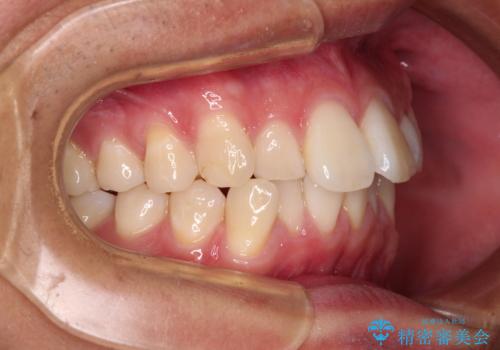

前歯のデコボコをインビザラインで綺麗に改善

- 上下前歯のデコボコとクロスバイトを気にして来院された患者様です。

インビザラインを用い、IPR(歯と歯の間を削る)と歯列全体を拡大させることで、歯並びを整えていくこととしました。

毎日22時間の装着時間を徹底してくださったのですが、左右ともに臼歯が咬合しなくなるという、インビザライン独特の症状が強く長く続いてしまい、終了するまでに長期間を要してしまいました。